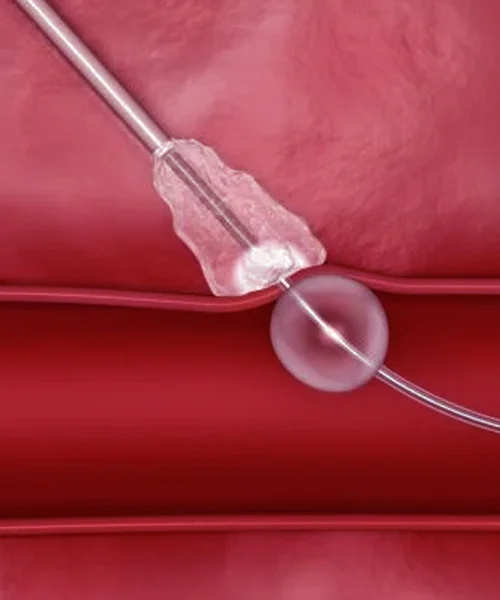

He holds prestigious qualifications including MBBS, MD in General Medicine, and DM in Cardiology, making him a highly skilled expert in interventional cardiology. Dr. Yogesh Nagendra has extensive expertise in procedures such as angiography, angioplasty, pacemaker implantation, Balloon Mitral Valvotomy (BMV), ECHO, and TMT, ensuring accurate diagnosis and effective treatment for every patient.